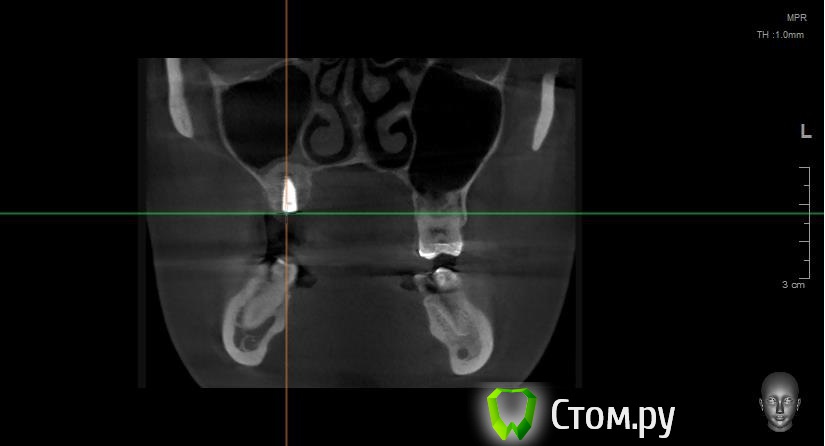

Майло Опубликовано 18 марта, 2014 Автор Поделиться Опубликовано 18 марта, 2014 (изменено) Здравствуйте, наконец сделала кт. Сегодня появилась небольшая боль над правой бровью (после лазера прошла, к вечеру появилась опять). Насморк и заложенность присутствуют. Еще сегодня опять поговорила со своим хирургом имплантологом. По симптомам сказал, что похоже присоединилась какая-то лор болячка и наверное надо сходить к лору. По кт сказал, что все нормально. Немного сужена пазуха справа, но учитывая, что я аллергичная, это нормально. Про капли типа Полидекса, сказал спросить у лора. Завтра я делаю последний лазер, по прежнему промываю нос Отривином Бэби (мне так удобней), пью кларитин, "выбиваю" нос по необходимости, но стараюсь пореже (2-3 раза в день). Еще он отдал кт через 2 недели после имплантации, на всякий случай прикреплю и этот снимок. Самый первый снимок кт был сделан через 2 недели после имплантации. Второй и третий сегодня. Подскажите, я так понимаю данное кт не показывает есть ли у меня гайморит? (к лору смогла записаться аж на 26-е) И все равно хотелось бы узнать ваше мнение по поводу состояния имплантов, есть ли там воспаление или "нагноение"? Изменено 18 марта, 2014 пользователем Майло Ссылка на комментарий

Майло Опубликовано 18 марта, 2014 Автор Поделиться Опубликовано 18 марта, 2014 (изменено) Решила еще добавить пару кадров своих пазух, вначале показалось что справа что-то есть (рис1), потом поняла это костный материал и импланты (рис2). Надеюсь так должно быть. И еще вопрос, может и "тупой", такое яркое свечение имплантов, особенно заметно на фото в профиль, это нормально? Изменено 18 марта, 2014 пользователем Майло Ссылка на комментарий

Bier Опубликовано 18 марта, 2014 Поделиться Опубликовано 18 марта, 2014 выглядит все неплохо, и пазуха чистая. Гайморита у вас нет. Сходите к ЛОРУ 2 Ссылка на комментарий

Bier Опубликовано 14 апреля, 2014 Поделиться Опубликовано 14 апреля, 2014 Покажите пазухи на кт свежем еще раз, в предыдущем сообщении вы другую пазуху показали, с зубами Ссылка на комментарий

Bier Опубликовано 14 апреля, 2014 Поделиться Опубликовано 14 апреля, 2014 Странно, у вас абсолютно чистая пазуха. Если у Вас есть фейсбук, могу вас сконтачить с более толковым ЛОРом Просто "зеленые сопли" о которых вы говорите должны где-то быть. Ссылка на комментарий